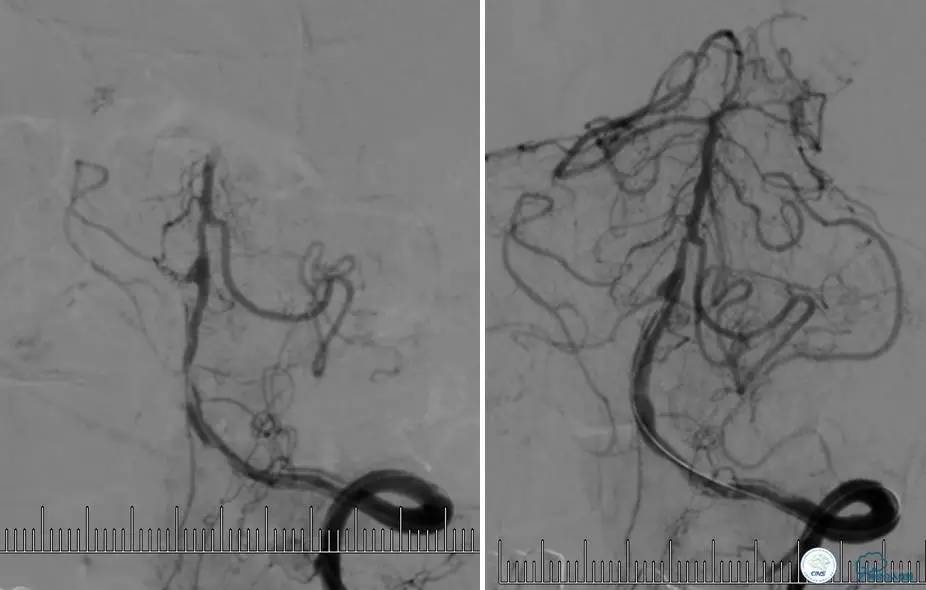

▼DSA示右侧椎动脉发育低下,弥漫性狭窄,可以看到左侧椎动脉反流,因此判断左侧椎动脉V4段CTO。

治疗:

微导丝穿过闭塞段,微导管造影,球扩闭塞段,置入Wingspan支架,血流完全恢复正常。

患者术后2天再次出现卒中发作,药物治疗好转,此后病情稳定。半年后复查DSA,见支架闭塞,侧支循环开放。患者一般情况好,mRS:1分。